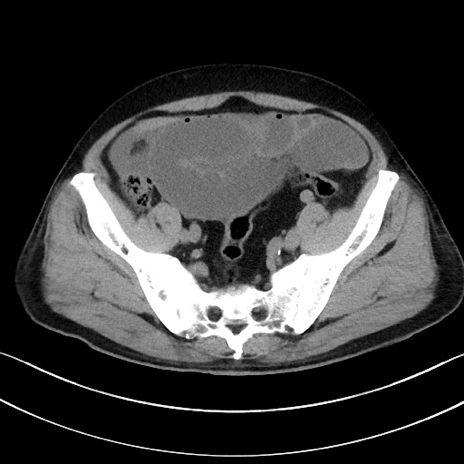

症例15(横断像)

【症例】70歳代男性

【主訴】腹痛

【現病歴】今朝から腹痛あり。全体的に痛い。特に左上の方。排ガスが今日はない。冷や汗が出る。

【既往歴】直腸癌術後

【身体所見】左側腹部〜上腹部に圧痛あり。腹膜刺激症状明らかなではない。軽度反跳痛。左下腹部に術後瘢痕あり。

【データ】WBC 7700、CRP 0.02